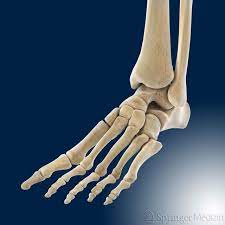

Fußknochen an der seite. Nachdem der erste Anlauf ein Eltern- Lehrerinnen- Team auf die Beine zu stellen im vergangenen Jahr an körperlichen Gebrechen gebrochener Fußknochen gescheitert war starteten wir in diesem Jahr einen neuen Versuch lauffreudige Menschen für den Hanauer Stadtlauf zu begeistern. Der Fuß besteht aus Fußwurzelknochen Mittelfuß und den fünf Zehen auch Vorfuß genannt. Der Fuss ist an der Stelle mit dem Körper verbunden wo Knochen des Rückfusses auf das Schien- und Wadenbein treffen Knöchel.

Andere Erkrankungen der Füße entstehen durch Krankheiten die viele Bereiche des Körpers betreffen wie Diabetes mellitus Gicht oder andere Arthritisformen. Die Knochen des Fußskeletts werden durch zahlreiche Bänder zusammengehalten und sind durch Gelenke miteinander verbunden. Alle von diesen Cookies erfassten Informationen werden aggregiert und sind deshalb anonym.

Den gesamten Komplex bilden außerdem Gelenke Fußwurzelgelenke Gelenke der Mittelfußknochen und Zehengelenke viele für die. Eine weitere Ursache für Schmerzen an der Fußaußenseite ist die Fraktur des fünften Mittelfußknochens. Der menschliche Fuß besteht aus 26 Knochen.